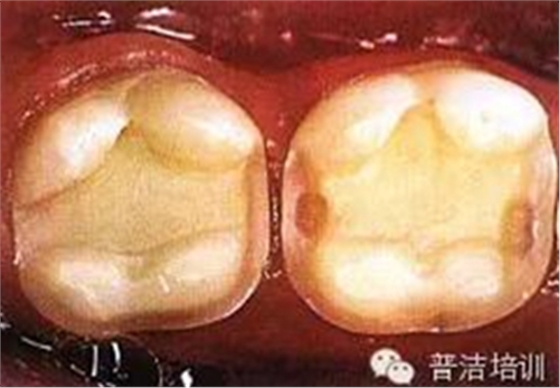

一、下頜后牙牙合面廣泛齲壞,檢查后決定行樹脂嵌體修復(fù)

二、去除齲壞的組織,可以使用送風(fēng)公司生產(chǎn)的齲齒檢測液來判斷齲壞的組織是否去除干凈